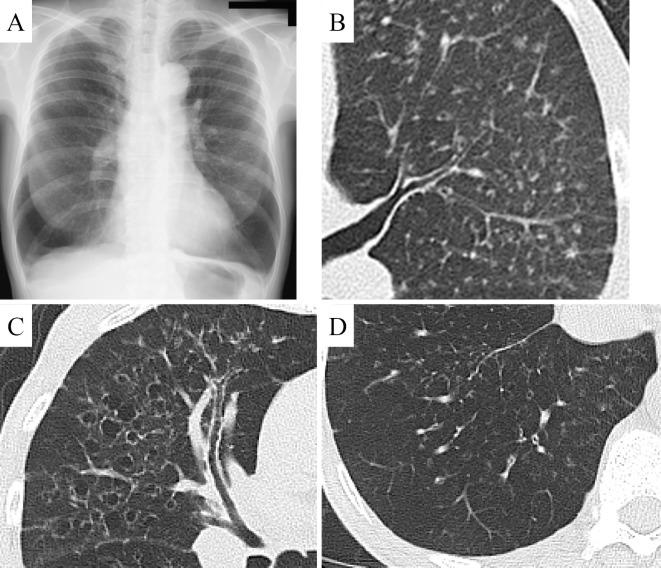

Idiopathic pulmonary hemosiderosis is characterized by repeated alveolar hemorrhaging. We herein report a 52-year-old Japanese woman who had shortness of breath, diffuse small nodules, thin-walled cysts, and bronchiolectasis. A surgical lung biopsy revealed peribronchial hemosiderosis, centrilobular emphysema, and fragile elastic fibers of the alveolar septa and small vessels. She ultimately underwent living-donor lung transplantation five years after the first visit.

特发性肺含铁血黄素沉着症的特征是反复肺泡出血。我们在此报告一例 52 岁日本女性,其症状为呼吸困难、弥漫性小结节、薄壁囊肿和支气管扩张。外科肺活检显示支气管周围含铁血黄素沉着症、小叶中心性肺气肿和肺泡隔及小血管脆弱的弹性纤维。她在首次就诊五年后最终接受了活体供肺移植。